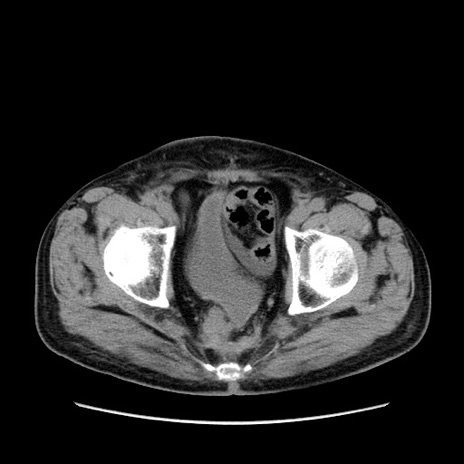

症例24(横断像)

【症例】80歳代男性

【主訴】左側腹部痛、嘔吐

【現病歴】本日早朝より左腹部に痛みあり。昼頃嘔吐認めたため、救急要請。

【既往歴】直腸癌(Mile手術)、胆摘

【身体所見】意識清明、BT 35.9℃、BP 221/93mmHg、SpO2 97%(RA) 、腹部:左ストーマ周囲に限局性の腹部膨隆あり。 膨隆部自発痛・圧痛あり・軟。

【データ】WBC 7700、CRP 0.09